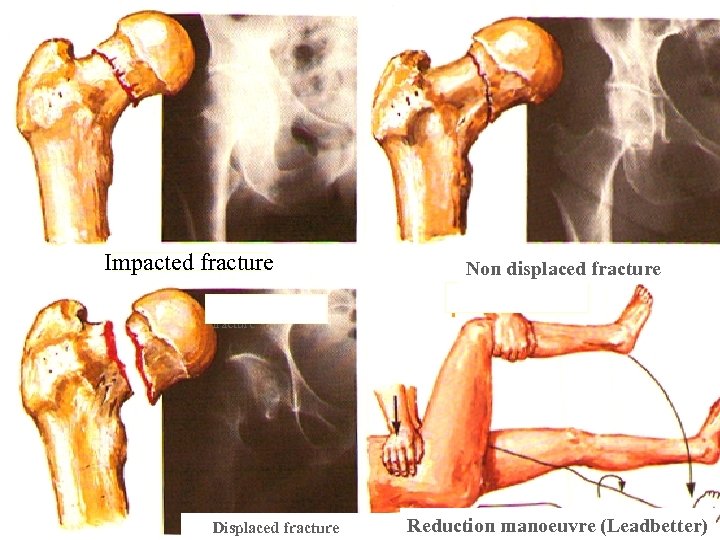

Impacted fracture Non displaced fracture Impacted fracture Displaced fracture Reduction manoeuvre (Leadbetter)

Impacted fracture Non displaced fracture Impacted fracture Displaced fracture Reduction manoeuvre (Leadbetter)